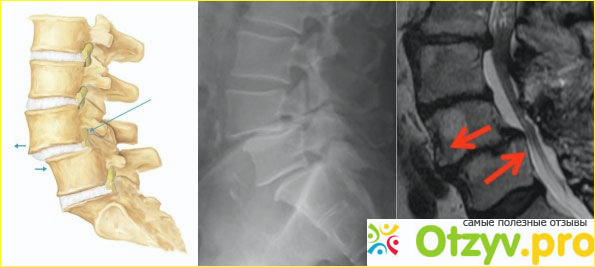

Мы еще где-то около часа ждали своей очереди и наконец-то дождались, врач ортопед осмотрел мой позвоночник и сказал, что есть ушиб, необходимо делать мануальную терапию, для меня это понятие было дальнее и где-то я по телевизору слышал, что это довольно опасно и можно только навредить своему здоровью, но у меня другого выхода не было. Я конечно же согласился на эту процедуру, напарники пошли на кассу, чтобы оплатить данную процедуру, честно не помню, сколько за это удовольствие мы оставили, но проблема вся в том заключалась, что мне порекомендовали пару дней задержаться в больнице, чтобы восстановить состояние позвоночника, я также на это согласился. Напарники поехали на объект, а я остался в данной больнице.

Мы заполнили с врачом анкету, далее он провел меня в отдельный кабинет, где сначала сделал массаж спины, были конечно же неприятные ощущения, после он приступил к процедуре выравнивания позвонков. Из-за удара фильтра у меня сместилось пару позвонков, которые нужно было вставить на место. И сказать честно, я даже ничего не почувствовал, все так быстро он мне вправил. Боли я также никакой не почувствовал. Процедура длилась минут 10, после чего он меня смазал каким то раствором и начал стучать по спине. Далее отправил в палату, где за мной приглядывали, периодически ортопед навещал меня, чтобы посмотреть изменения, важно было то, чтобы вправленные позвонки сохранили свое положение и не деформировались. На второй день мне также сделали массаж и затянули специальным корсетом меня, чтобы получить устойчивость позвонков.